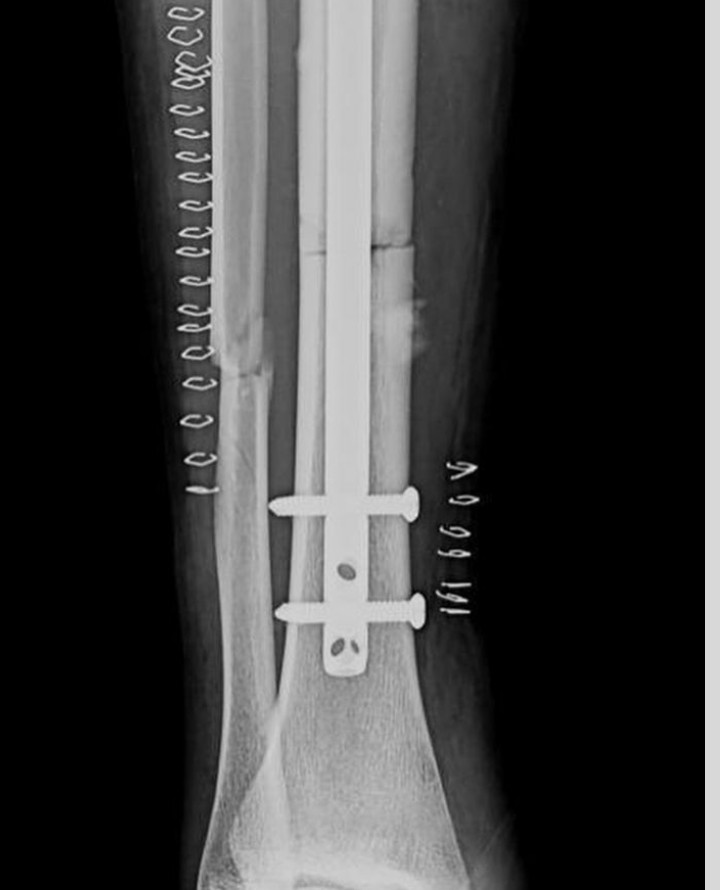

‘Igufwa ryahise ricika mo kabiri’  Dore amafoto yo mu byuma byo kwa muganga agaragaza uburyo igufwa rya Kimenyi Yves ryatandukanye ubwo yavunikaga

Ubwo Kimenyi Yves yari arimo ashimira Imana n’abantu bamubaye hafi mu bihe ari gucamo, abinyujije ku rukuta rwe rwa Instagram yasangije amafoto y’uburyo igufwa rye ryabaye ubwo yavunikaga.

Kimenyi yavunitse mu mukino As Kigali riheruka gukinamo na Musanze Fc bikarangira Musanze itsinze As Kigali igitego kimwe ku busa.